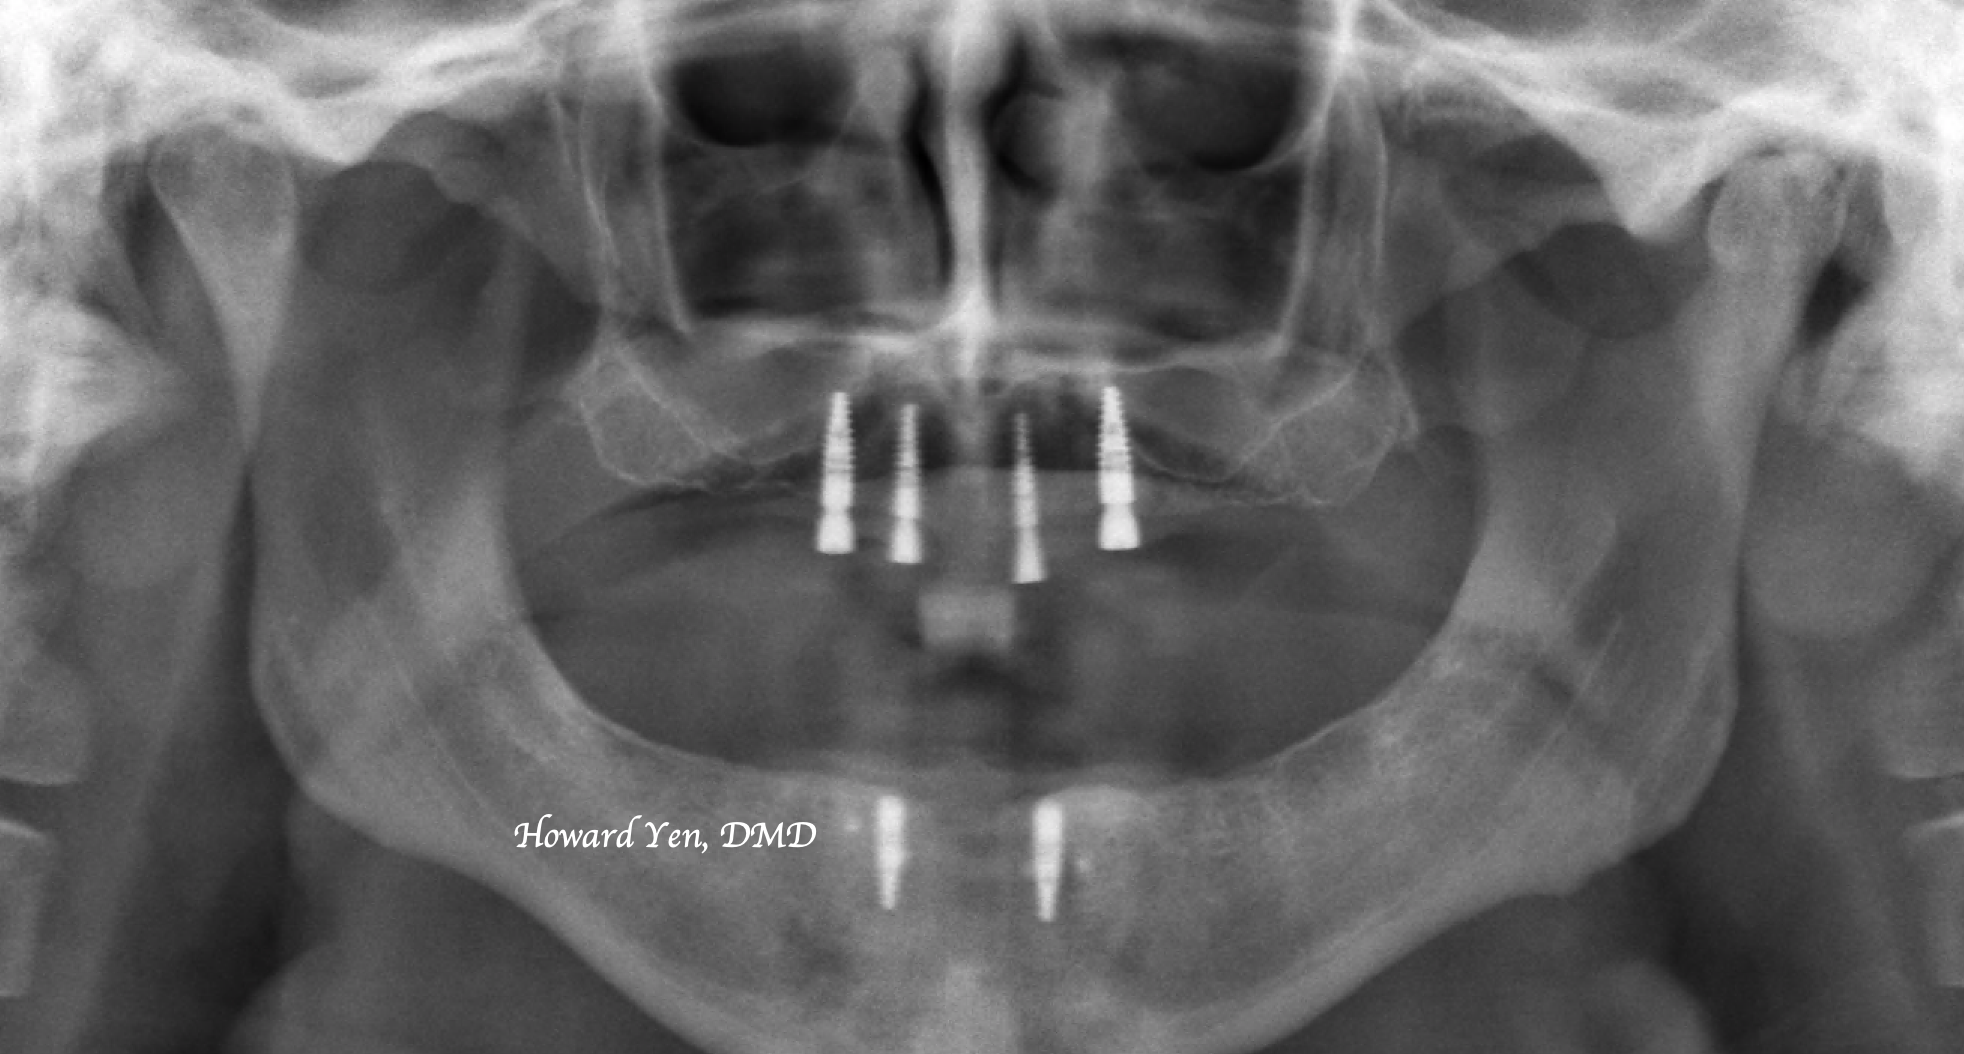

Upper & Lower Overdenture Implants